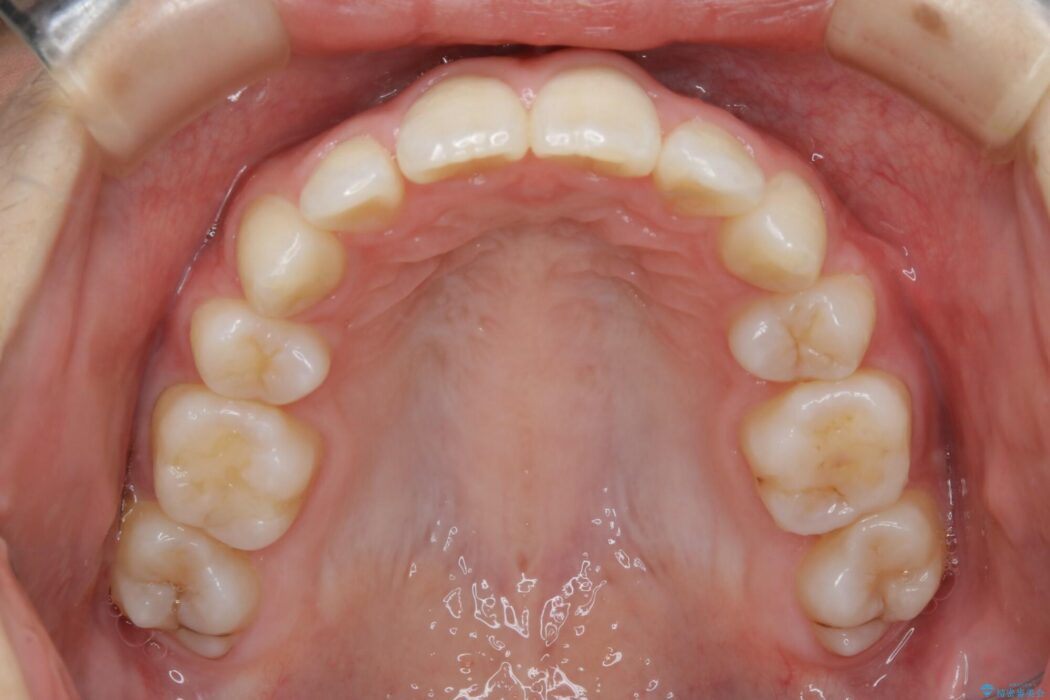

検査したところ歯に対して骨が上顎・下顎共に小さいことがわかりました。

それによりスペースが少なく歯列がガタついたり前方傾斜する生え方となっていました。

よって本症例では抜歯により歯の本数を減らすことにより整えるスペースを確保してワイヤー装置にて歯列矯正を行うこととしました。

顔貌のビフォーアフターでもわかるように口元の出っ張りが改善され、患者様にはとても喜んでいただけました。

横顔であったり笑った時の印象にも変化があるため、同様のお悩みを抱えている方はぜひご相談ください。